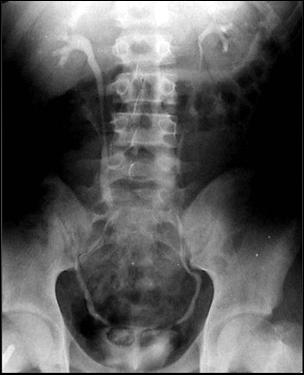

1. Diagnosticul diferential cu litiaza vezicala radiotransparenta

Ecografia vezicii urinare evidentiaza imagine hiperecogena, cu con de umbra posterioara (calcul)

Figura 54. Imagine radiotransparenta (2,5/1,8 cm, vizibila pe cistografie) |